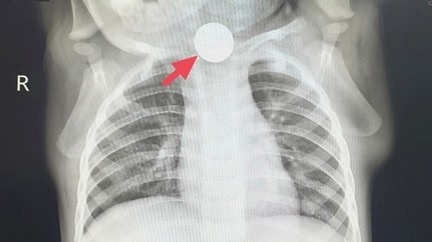

“稳妥起见,先去拍个胸片,排除肺部问题!”门诊医生叮嘱家长,心里却始终悬着一块石头。没想到,这份胸片报告带来的不是安心,而是惊天发现:冬冬食道上段,赫然卡着一枚硬币!

瞬间真相大白:所谓的“厌食”,是硬币卡喉导致吞咽疼痛,孩子根本不敢进食;频繁流口水是因为吞咽受阻,口水无法正常下咽;咳嗽则是口水呛入气道引发的反应。此前的“受凉”“胃口差”,全是误导判断的假象!